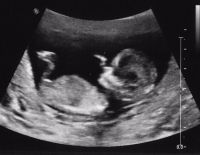

Siêu âm thai 12 tuần là một trong những mốc rất cần thiết và quan trọng đối với các mẹ bầu. Siêu âm trong thời điểm này giúp các bà mẹ nắm rõ mọi vấn đề về sự phát triển của thai nhi. Để từ...

Siêu âm thai 20 tuần có tác dụng gì và nên siêu âm thế nào?

Siêu âm thai 20 tuần là một bước ngoặt lớn của cả mẹ bầu và thai nhi, có ý nghĩa cực kỳ quan trọng. Nếu bạn vẫn chưa biết rõ về lợi ích khi siêu âm thai 20 tuần và không biết nên siêu âm...